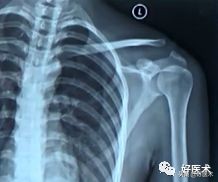

- X线照片:左侧:术前;右侧:术后